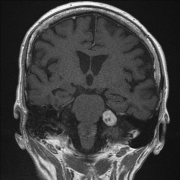

听神经瘤约占颅内肿瘤的7%。听力丧失、耳鸣、眩晕和不稳定是其早期症状。其他症状只出现在肿瘤长大后压迫大脑。早期诊断取决于MRI和听力学检查,包...

听神经瘤是什么? 大多数听神经瘤起源于前庭神经的上前庭。通过神经鞘瘤生长,内听道扩大,内听道逐渐生长,然后进入颅内。根据其生长特点,内听道...

据统计,小脑角肿瘤占全部颅内肿瘤的6-10%。桥小脑角(CPA)是指脑桥、延髓、小脑的交界处,位于后颅窝的前外侧,是由前内侧的桥脑外缘、外后方的岩...